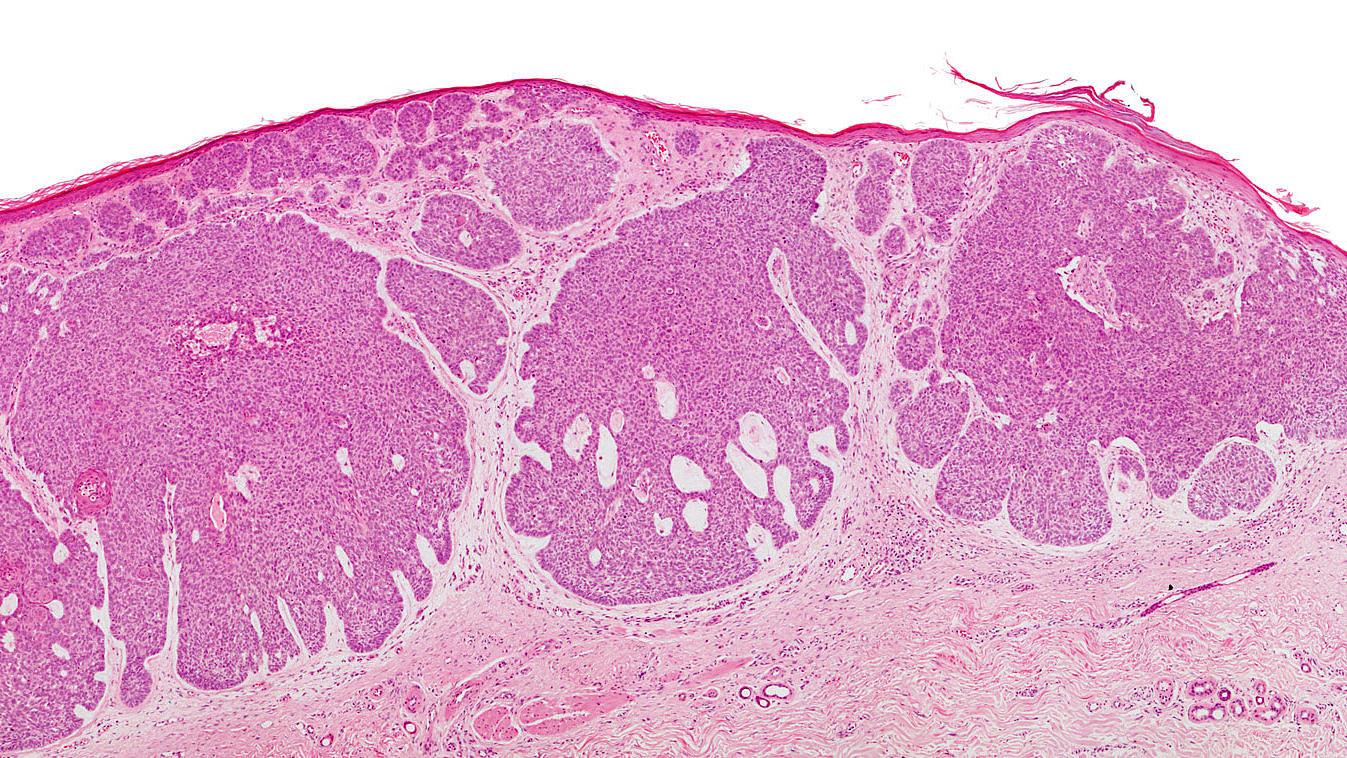

Malignes Melanom („schwarze Hautkrebs“)

Im Gegensatz zu den weißen Hautkrebsarten verhält sich das Melanom, der "schwarze Hautkrebs" sehr viel aggressiver. Das Melanom kann sich schon sehr viel früher über das Lymphgefäßsystem oder die Blutbahn im Körper ausbreiten, wodurch dieser Tumor sehr viel gefährlicher ist.

Auch hier wird man daher eine sehr rasche und vollständige Exzision mit einem Sicherheitsabstand vornehmen. Bei sehr frühen (dünnen!) Tumoren führt dies in aller Regel zu einer Heilung. Bei nicht wenigen Patienten haben sich aber zum Zeitpunkt der Entdeckung schon Metastasen gebildet. Daher spielen neben einer Operation eine Immuntherapie und gegebenenfalls eine Chemotherapie oder eine Bestrahlung bei der Behandlung eine wichtige Rolle. Relativ neu sind sogenannte zielgerichtete Medikamente, die sich gegen besondere Eigenschaften der Tumorzellen richten. Patienten mit fortgeschrittener Erkrankung profitieren von diesen neuen Arzneimitteln.

Maligne Melanome sind allerdings im Gegensatz zu weißem Hautkrebs relativ seltene Tumore: 2014 erkrankten nach Angaben der Gesellschaft der Epidemiologischen Krebsregister und des Zentrums für Krebsregisterdaten am Robert-Koch-Instituts etwa 22.220 Menschen an einem Melanom.